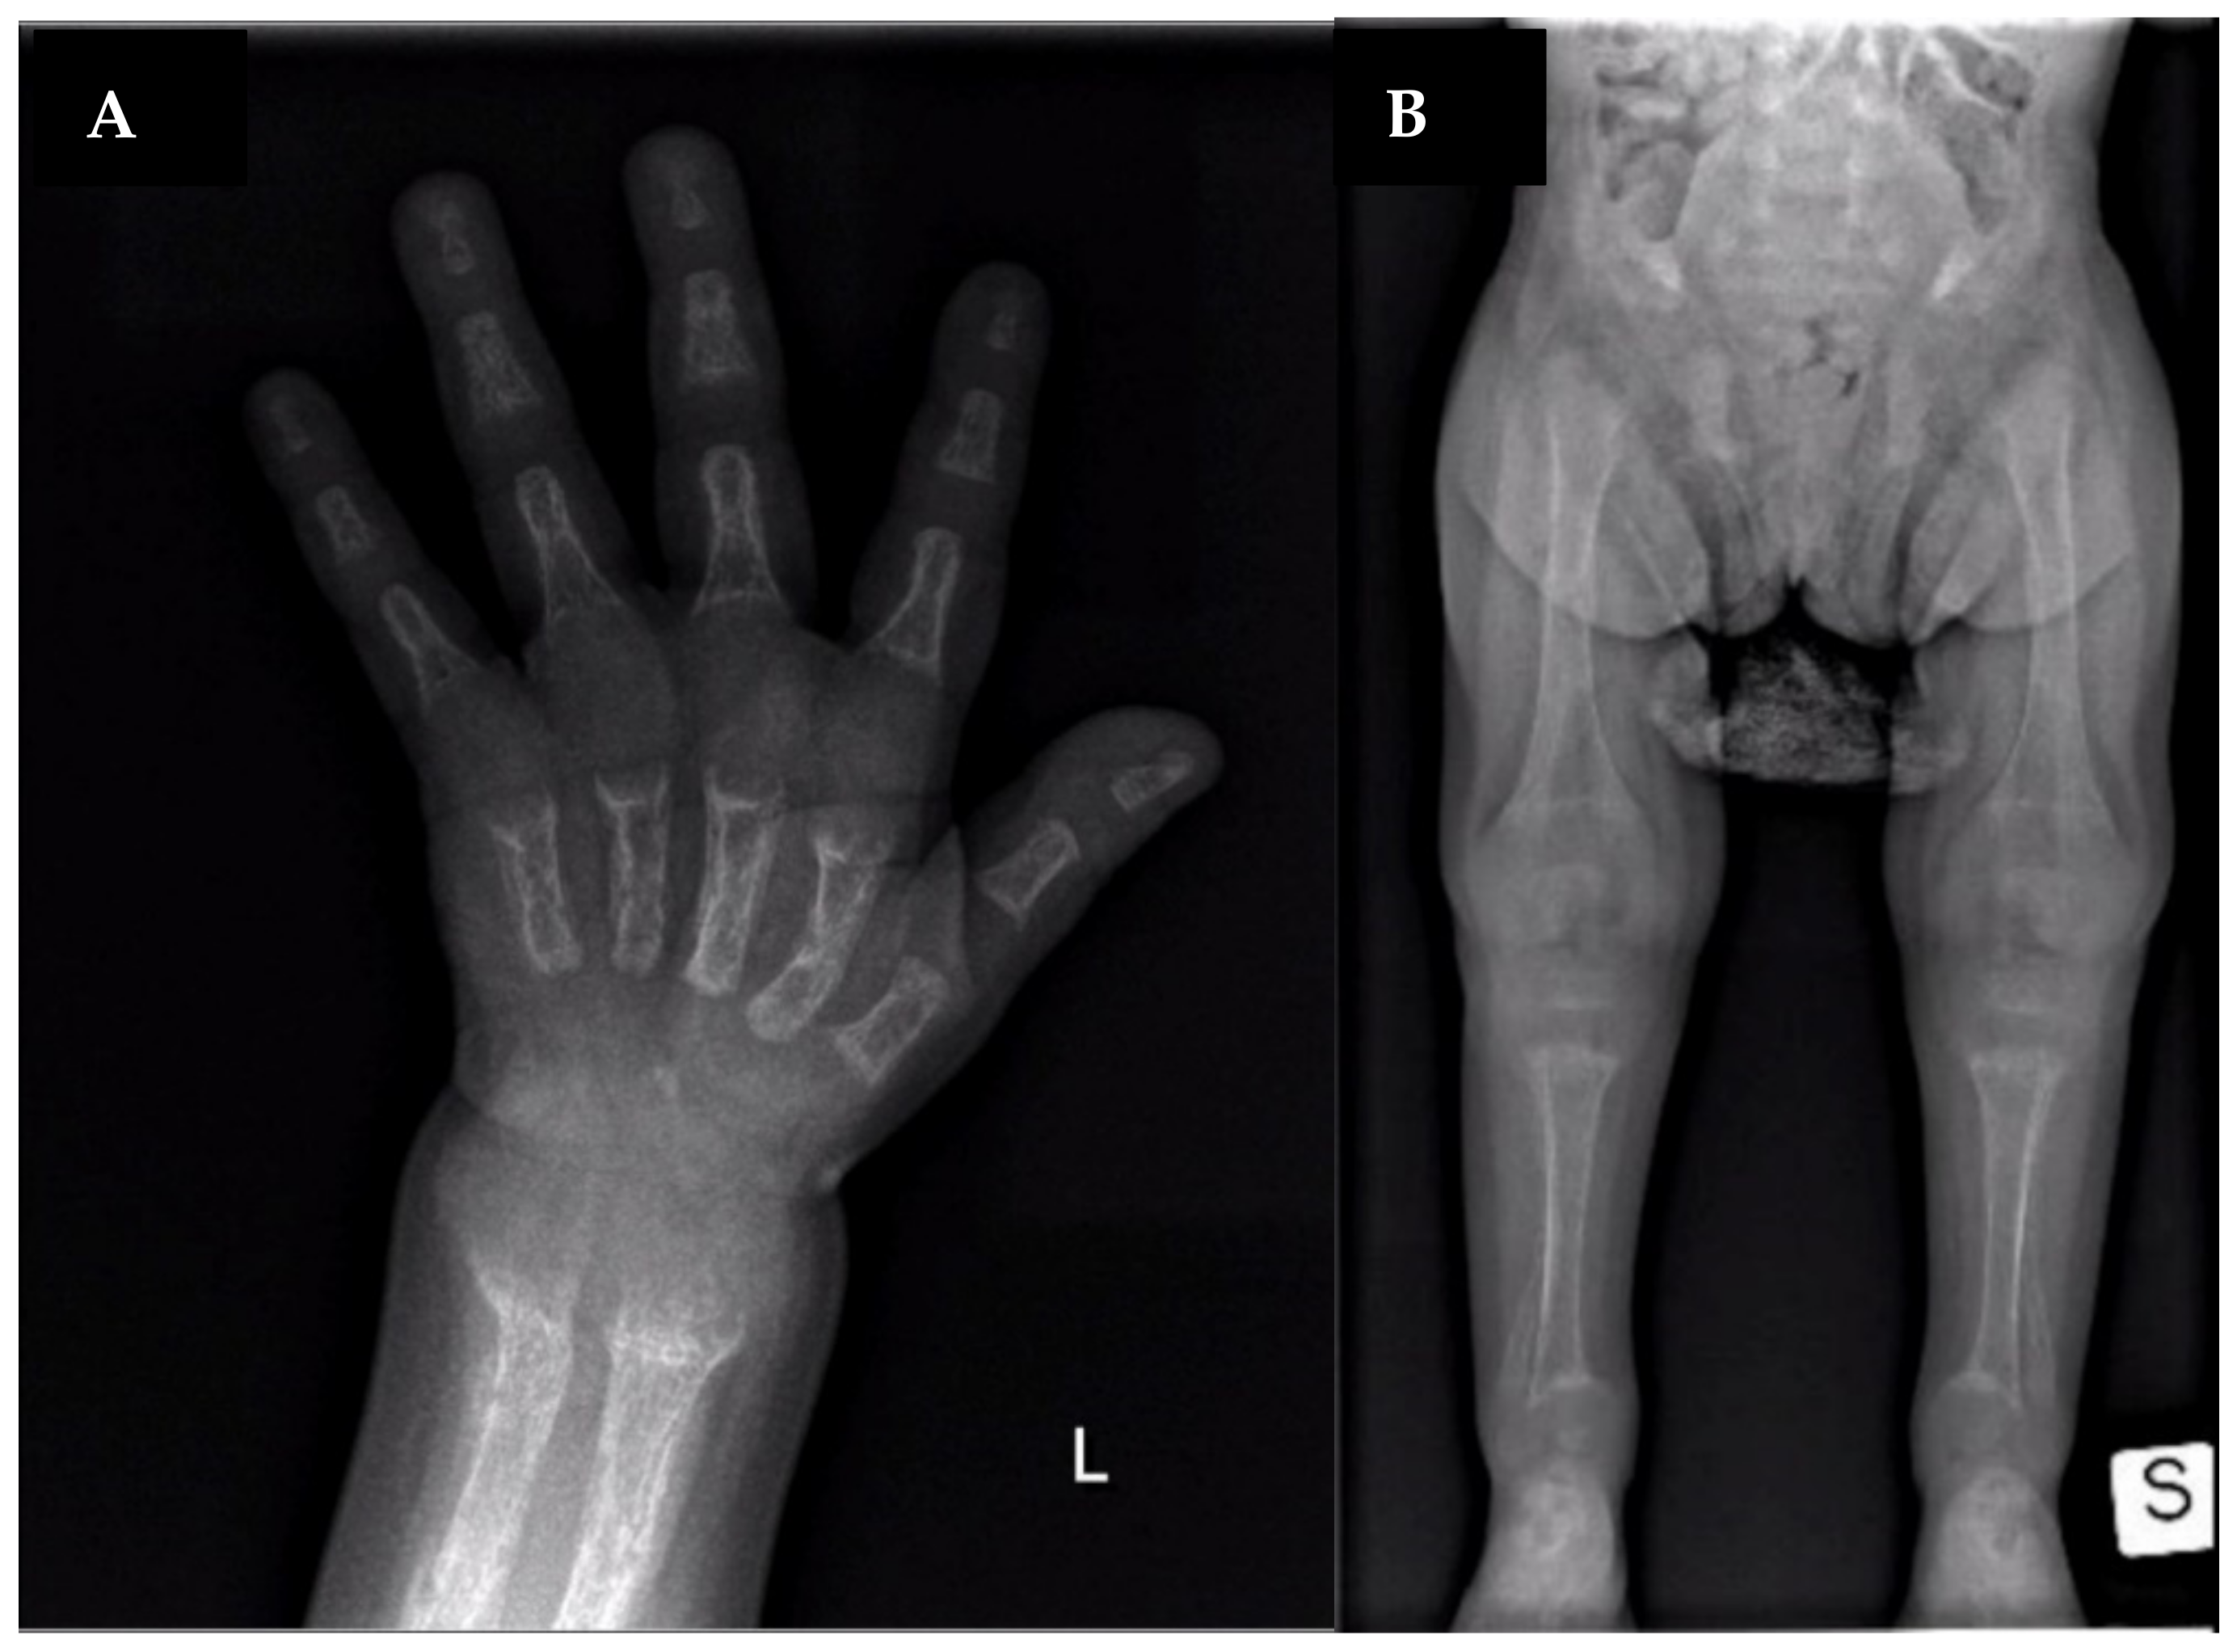

| Clinical features | Bone pain, osteomalacia ankle soreness, low back pain, fatigue, pseudofractures | Rachitic lesions at the wrists and knees, growth retardation | Genu valgum, decreased energy, moderately severe rickets | Rachitic rosary, metaphyseal widening, fraying and cupping of the ulna and the distal femur | Genu varum, growth retardation | Bone deformities, dental hypoplasia, frontal bossing, short stature, pectus carinatum, anterior bowing of both legs, pelvis retroversion | Bone deformities, dental hypoplasia, frontal bossing, short stature, pectus carinatum, anterior bowing of both legs | Genu varu, severe rickets, waddling gait | Rickets, short stature, pain in spine/hips/legs and difficulty in walking, kyphoscoliosis, proximal muscle weakness in all four limbs, and genu varus, deformity of bilateral lower limbs | None | Hypotonia, Rickets, growth retardation |

| Treatment | Vitamin D 50.000–100.000 U/day | Vitamin D 25.000–50.000 U/day, then vitamin D 5–25.000 U/day (vitamin toxicity) | Vitamin D 30.000–50.000 U/day At 11 ys calcitriol 0.25–0.5 mcg twice daily | Calcitriol 0.125 mcg/day Oral phosphate 220–400 mg/day | Oral phosphate + Calcitriol (doses not available) | Oral phosphate (doses not available) | Oral phosphate (doses not available) | Oral phosphate 64 mg/kg/day Alfacalcidol 20 ng/kg/day At 8 ys iron sulfate solution | Vitamin D and calcium till 5 y of age. Since age of 13: Phosphate 60 mg/kg/d in four divided doses and calcitriol 60 ng/kg/d in three divided doses for 6 months | NA | Oral alfacalcidol (0.020 mcg/kg/day) and oral phosphate (30 mg/kg/day, divided in 3 doses) |

| Symptoms Resolution | No | Yes | Yes | Yes | Yes | Yes | Yes | Yes | Yes | NA | Yes |

| Age at last follow-up visit (H/W if available) | 22 ys H: 163.1 cm W: 65.9 kg | 20 ys | 19.75 ys H 178.8 cm | 8 ys | 3 ys 6 mo | 9 ys H: 138 cm | 12 ys H: 150 cm | 11.5 y H: 125.3 cm (−3.23 SDS) W: 26.2 kg (−2.2 SDS) | 13 y | NA | On going |